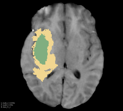

Deep neural network models used for medical image segmentation are large because they are trained with high-resolution three-dimensional (3D) images. Graphics processing units (GPUs) are widely used to accelerate the trainings. However, the memory on a GPU is not large enough to train the models. A popular approach to tackling this problem is patch-based method, which divides a large image into small patches and trains the models with these small patches. However, this method would degrade the segmentation quality if a target object spans multiple patches. In this paper, we propose a novel approach for 3D medical image segmentation that utilizes the data-swapping, which swaps out intermediate data from GPU memory to CPU memory to enlarge the effective GPU memory size, for training high-resolution 3D medical images without patching. We carefully tuned parameters in the data-swapping method to obtain the best training performance for 3D U-Net, a widely used deep neural network model for medical image segmentation. We applied our tuning to train 3D U-Net with full-size images of 192 x 192 x 192 voxels in brain tumor dataset. As a result, communication overhead, which is the most important issue, was reduced by 17.1%. Compared with the patch-based method for patches of 128 x 128 x 128 voxels, our training for full-size images achieved improvement on the mean Dice score by 4.48% and 5.32 % for detecting whole tumor sub-region and tumor core sub-region, respectively. The total training time was reduced from 164 hours to 47 hours, resulting in 3.53 times of acceleration.